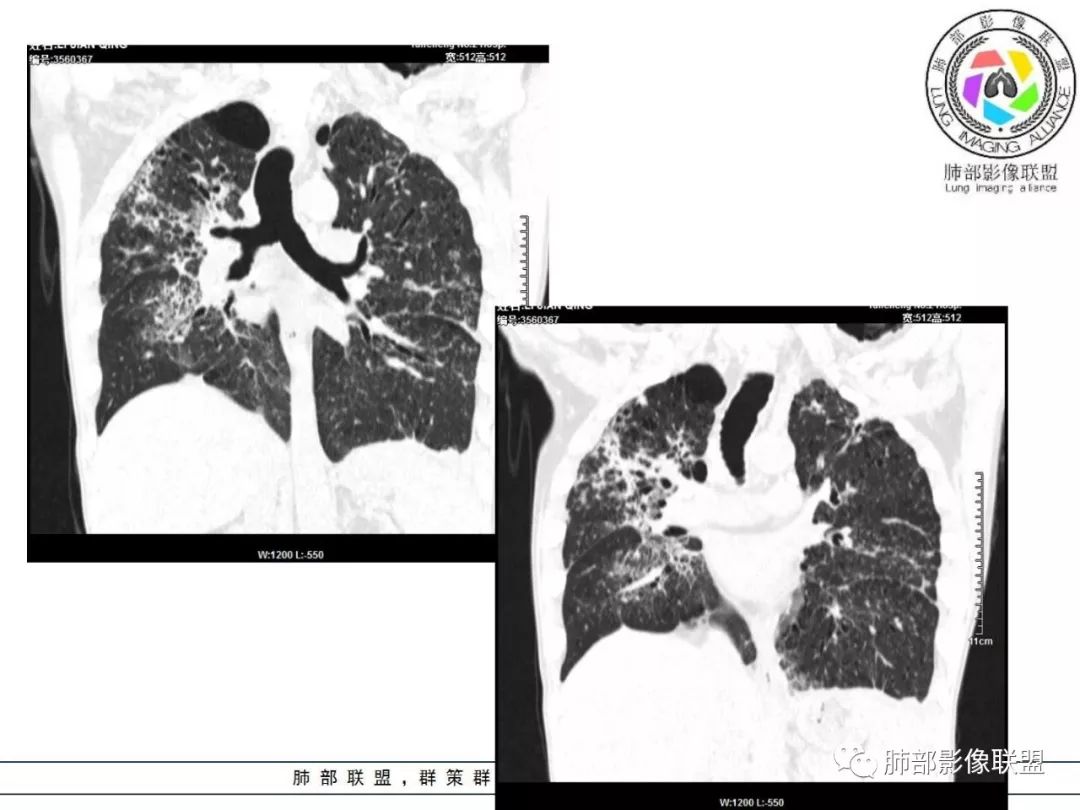

胸部CT:两肺弥漫病灶,磨玻璃影,少许实变,部分累及胸膜,磨玻璃区可见囊?少许胸腔积液,两肺可见结节,支气管血管束增粗,小叶间隔增厚,支气管走形有扭曲扩张,可见纤维化。气肿、大泡。考虑:感染性病变,PCP?查下HIV,CD4,G等。鉴别结核、结缔组织病肺浸润。

胸部CT:两肺弥漫病灶,中央间质分布为主,部分位于胸膜及叶间裂旁,磨玻璃影,斑片影,部分实性结节,肺气囊,支气管血管束增粗,小叶间隔增厚,叶间裂不均匀增厚,支气管走形有扭曲扩张,可见纤维化、气肿、大泡。考虑:LIP加MALT。鉴别PLCH、PCP、结核、结缔组织病肺浸润。

双肺肺气肿背景,双肺弥漫分布磨玻璃及实变密度,病灶沿血管支气管束及胸膜下分布为主,部分病灶以平直收缩为主,局部支气管稍扩张,管壁增厚,小叶间隔增厚,结合临床病史,考虑炎性病灶,感染伴病灶机化?结核?NTM?

中老年男性,发热1月余,双肺弥漫性病变,多发网格、结节、斑片状实变影及磨玻璃影,胸膜下及中轴间质都受累,支气管血管束增粗、变形,支气管扩张,叶间裂及小叶间隔增厚,整体间质性改变明显,考虑结核?OP、LIP?进一步除外PCP、肿瘤、结节病等。

中老年男性,发热时间长,有高热,血沉不快,双肺弥漫性病变,多发网格、结节、斑片状实变影及磨玻璃影,胸膜下、中轴间质及小叶间隔增厚,支气管血管束增粗、变形,牵拉性支气管扩张,叶间裂及小叶间隔增厚,第一考虑弥漫性间质病变,炎症?结核?结节病?综合考虑,结核排前面,多形态,病程长,间质增厚明显,较一般感染硬结感强。不确定的地方在,病灶范围广,间质累及严重,而且病人高热。其次考虑感染,或特殊菌感染。结节病不除外。

病灶呈片状磨玻璃密度影,呈典型的烟花征。磨玻璃影密度偏高,有网结节样改变,与正常肺实质分界清楚,且常见相对高密度的勾画。

烟花征分为3肿类型:晕征、反晕征及均匀分布。

病变一般沿血管支气管束分布或小叶分布,一般上肺多于下肺(这与常见继发性肺结核分布相若)。

常会伴有其他继发性肺结核病灶,如斑片影、结节影,树芽征,新旧不等改变。

临床中毒症状常较轻,病变相对稳定,增强扫描常无异常强化。

2. 肺气肿背景(小叶中心性肺气肿);双肺多发病灶整体沿血管支气管束及胸膜下分布,以上叶及下叶背段分布为主,有实变及GGO,边界清楚,有树芽,小叶间隔及中央间质增厚,叶间裂见到多发结节,部分支气管不规则牵拉扩张,提示病灶纤维化明显,结合临床病史,考虑病灶为间质性感染,肺门及纵隔内有钙化淋巴结,小叶间隔结节,考虑淋巴道增值性疾病可能,综合常规要怀疑间质性肺结核。

3. 该病例临床提示感染,有支气管扩张,提示纤维化,需要与感染后的OP鉴别,但是OP病灶常无结节感;间质性肺结核有时与不典型结节病鉴别也比较困难,结节病常以双肺门淋巴结增大为特征。临床上结核发病率较高。